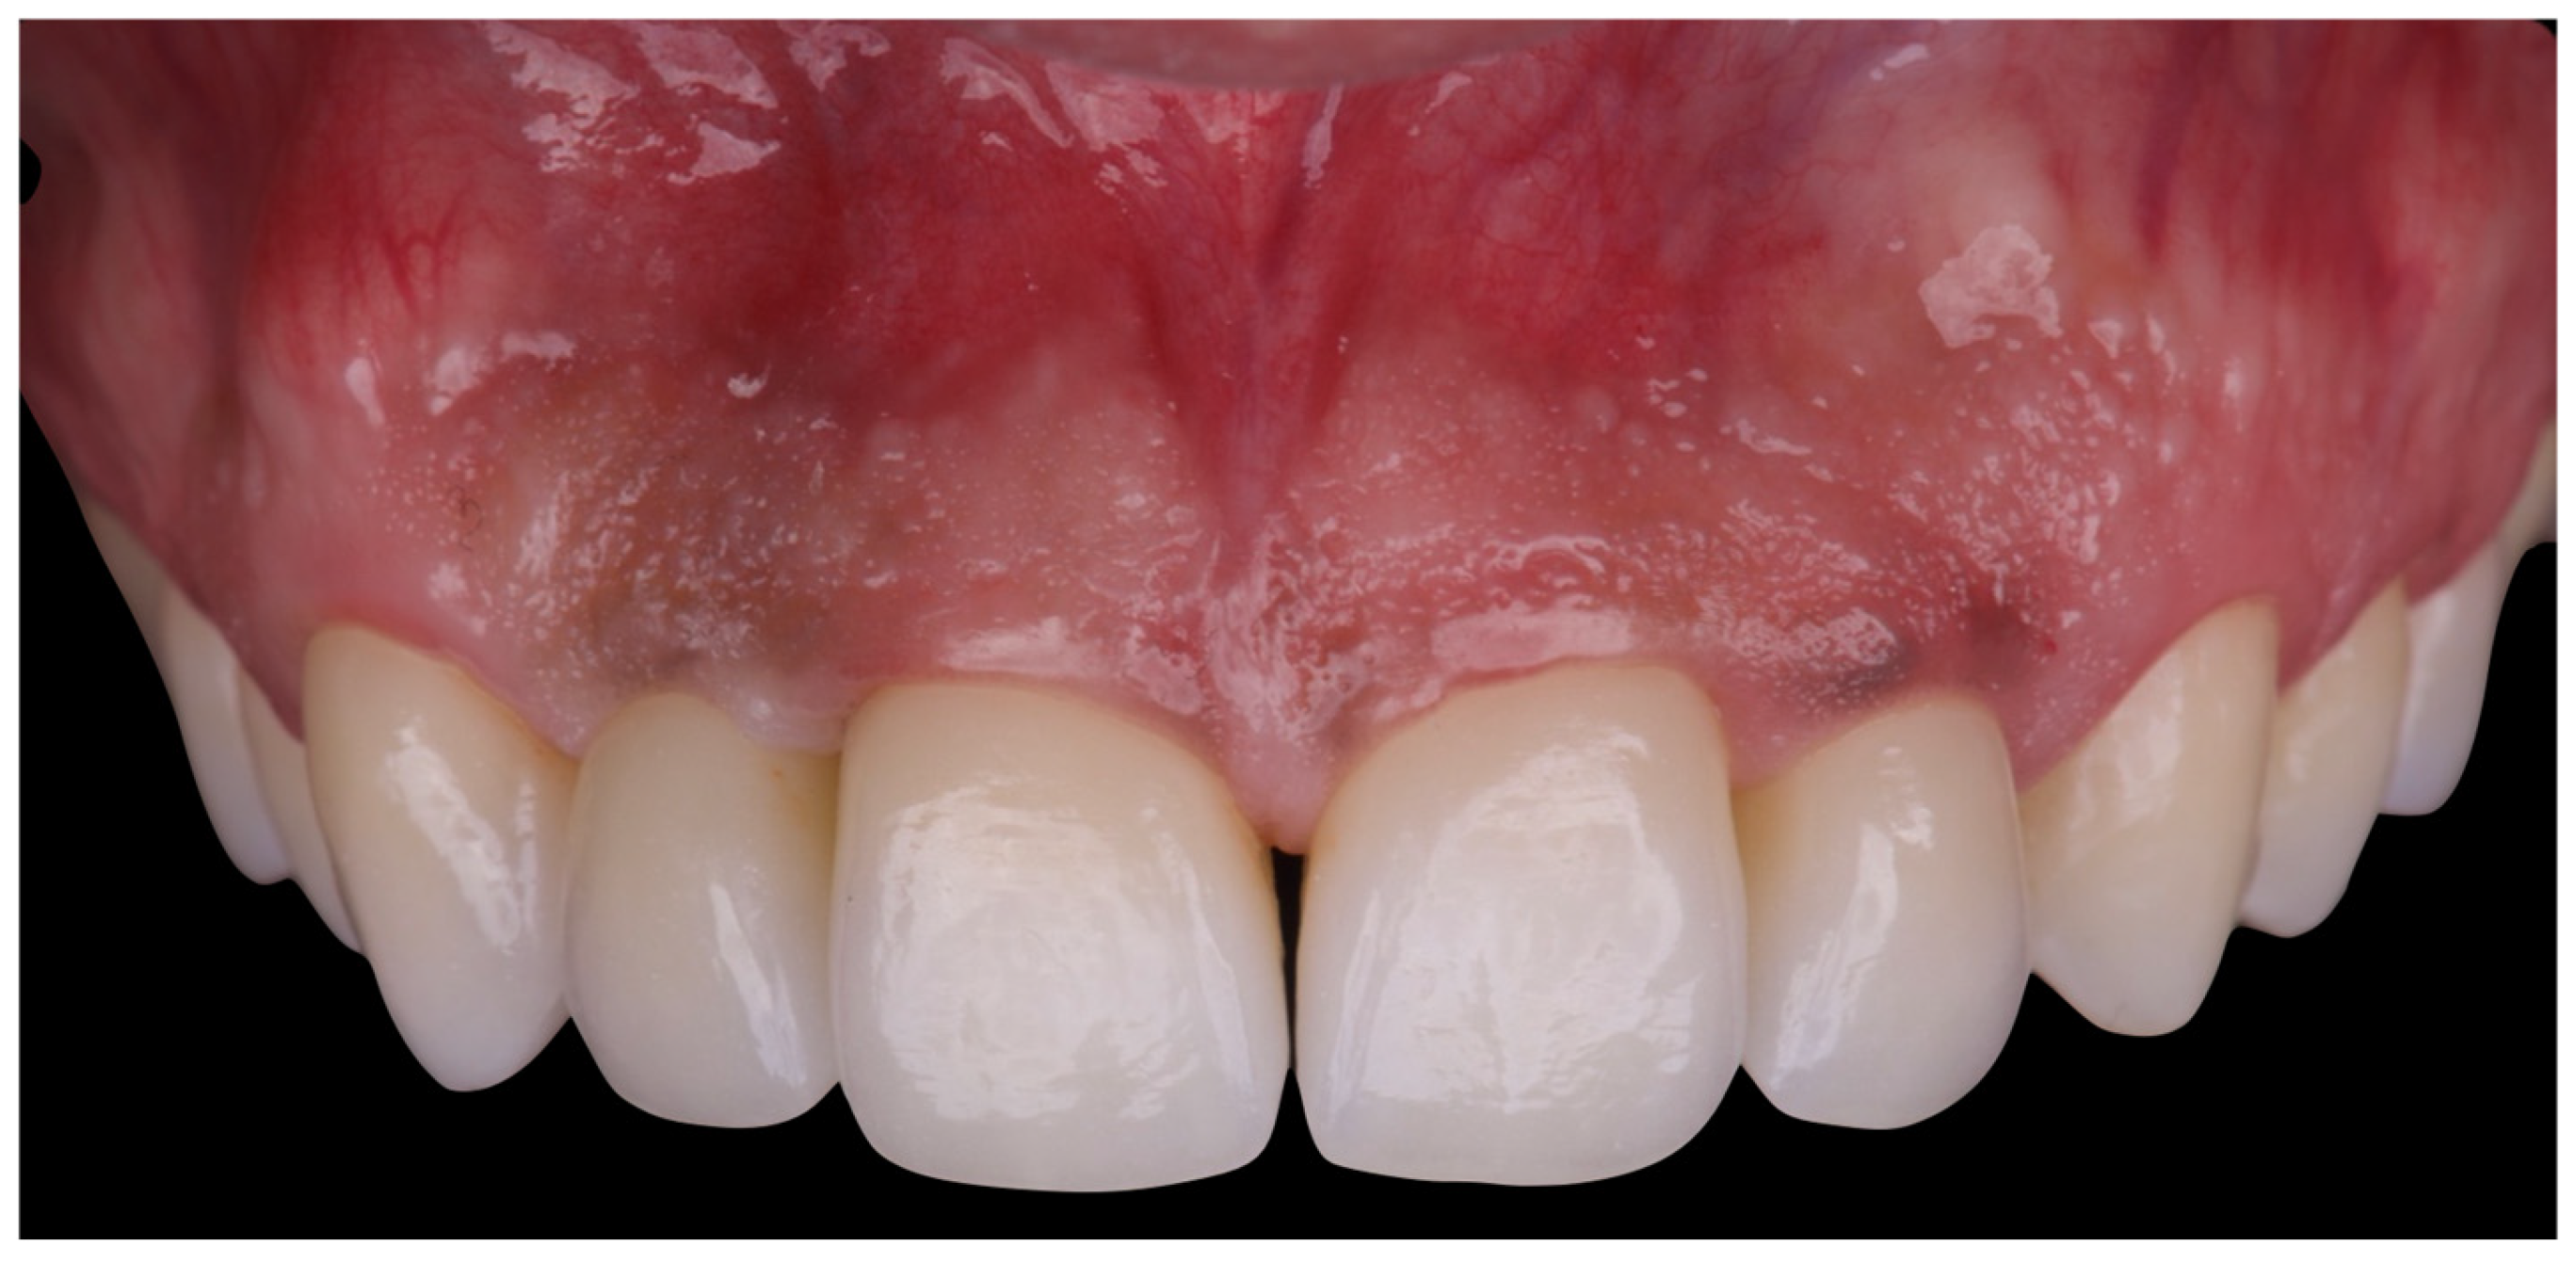

The initial aesthetic evaluation revealed a 7 mm incisal display at rest, a flat incisal edge morphology, a high smile line, and a smile width encompassing ten teeth with normal buccal corridors. The facial midline was aligned with the interincisal midline, although a diastema was observed between teeth 1.1 and 2.1 (Figure 5).

Figure 5. Clinical image demonstrating coincidence of the facial midline with the maxillary interincisal line. A midline diastema is evident.

Figure 18. Final intraoral image.

Figure 19. Intraoral image at four-year follow-up.